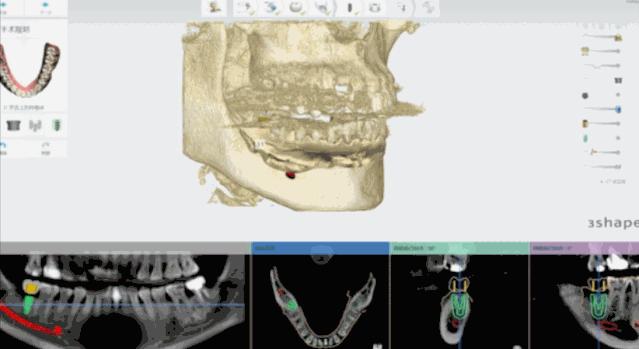

日照口腔医院种植中心配置先进的种植手术室,为患者提供各种类型的种植义齿修复,在日照市最早开展口腔种植技术,采用先进的医疗技术装备和世界一流的种植系统,配备有丹麦3shape口内扫描仪、Yoshida激光治疗仪、卡瓦(KaVo)锥形束CT、超声骨刀等国际先进仪器和设备,装备有瑞士士卓曼等多套国际种植系统,同时配备国际一流的消毒供应室,为疑难复杂病例的诊治提供了必要条件。

医院开展CAD/CAM数字化种植导板技术,通过整合数字化影像、cbct 数据以及数字化加工技术的新型种植导板,充分考虑到了颌骨条件、口腔解剖结构以及修复效果的结合,且精确度高,手术安全性高。